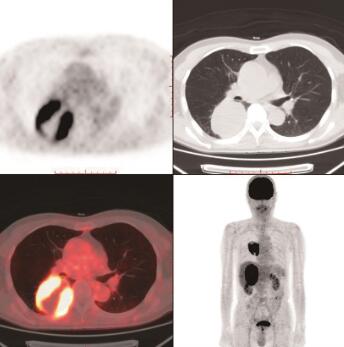

图1 右肺下叶转移瘤

18F-FDG PET/CT横断位示右肺下叶背段软组织肿块,内后缘与胸壁相连,代谢异常增高,SUVmax为19.5

右肺下叶背段见一软组织肿块影,大小约6.2cm×5.6cm×8.5cm,上份见钙化点,内后缘与胸壁相连,邻近胸膜增厚,肿块放射性不均匀增高,SUVmax约19.5,其内见大片液化坏死区呈放射性缺损区(图1)。右肾上腺区见一巨大稍低密度肿块影,大小约8.0cm×6.6cm×11.1cm,边缘见钙化灶,与右肾及肝脏分界不清,肿块放射性不均匀增高,SUVmax约18.9(图2)。